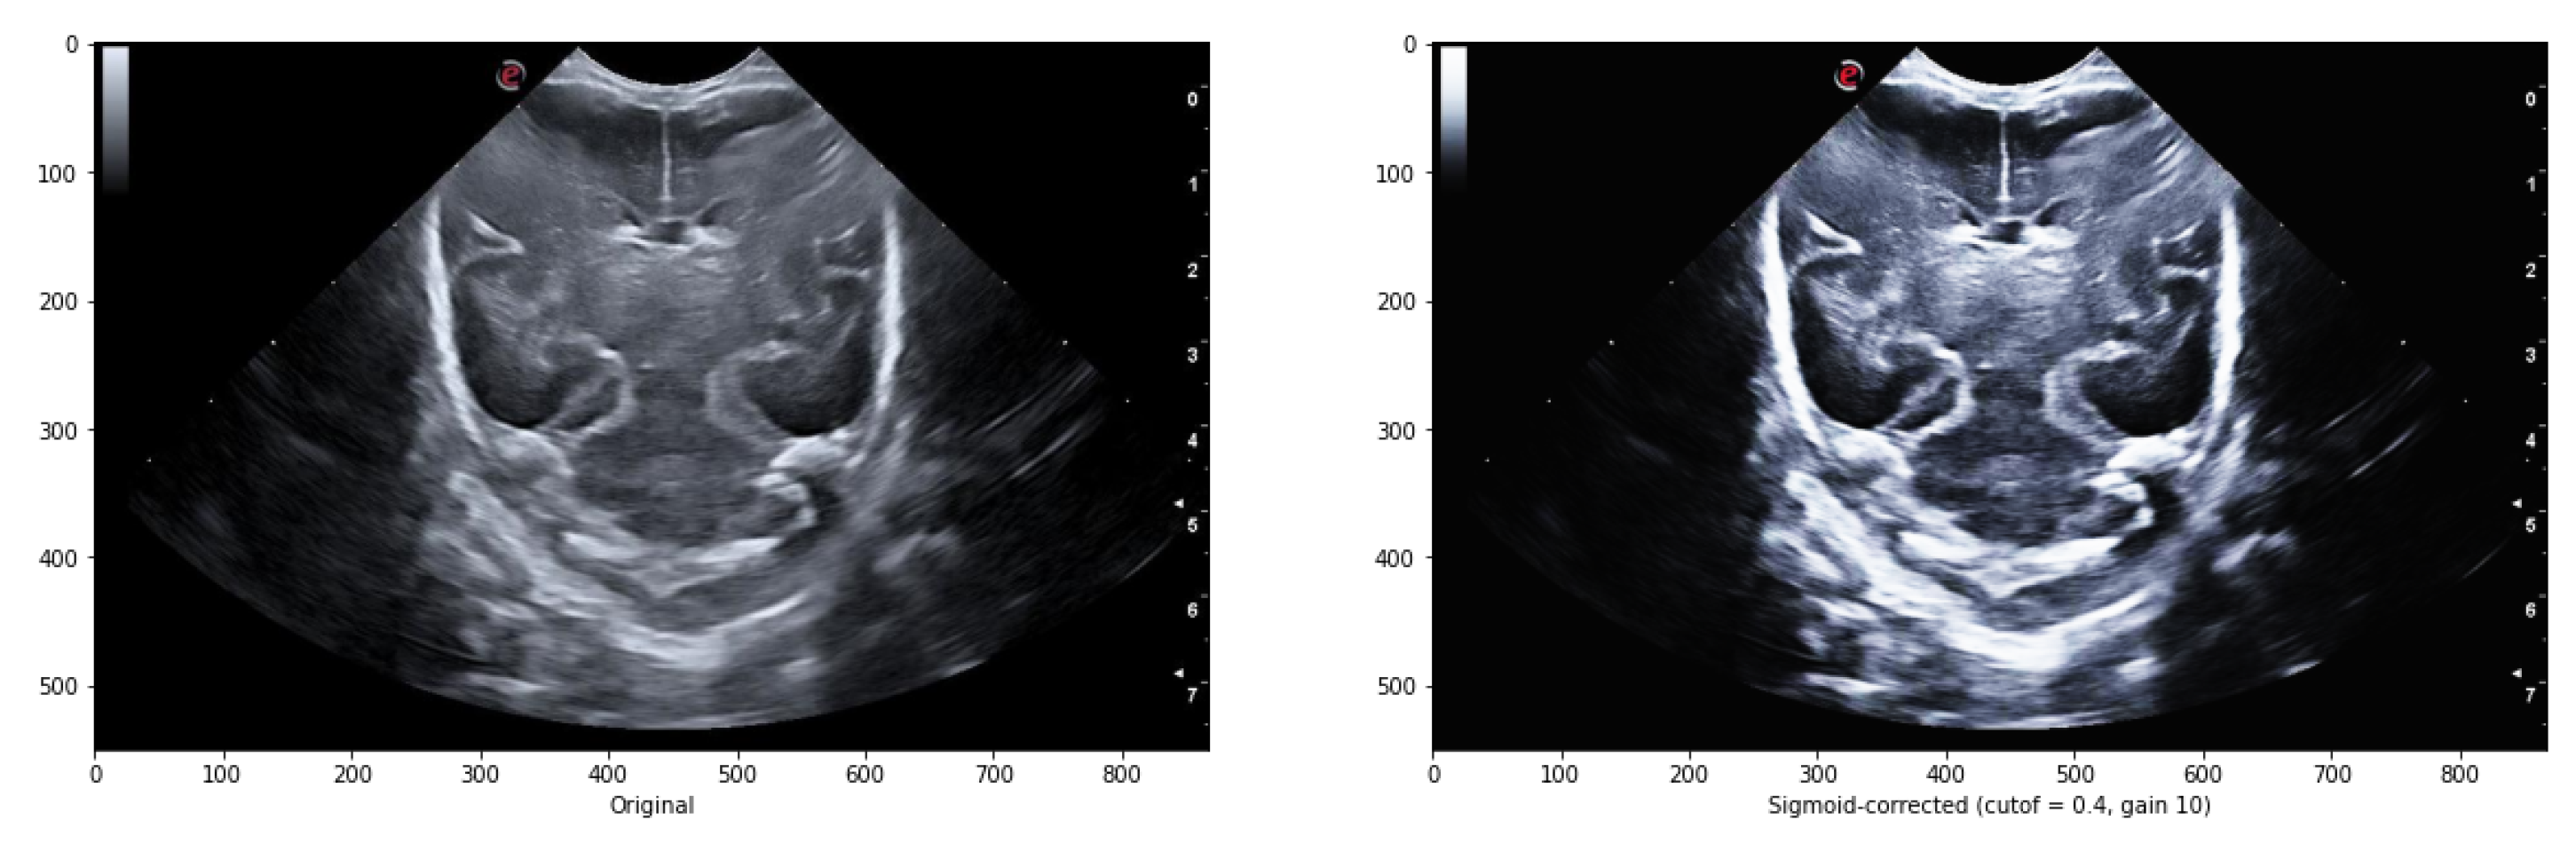

There exist multiple methods to enhance the contrast between the background and elements in ultrasound images. One of such methods is Sigmoid correction, also referred to as Contrast Adjustment (Equation 3).

The c u t o f f parameter determines the cut-off point of the Sigmoid function, shifting the characteristic curve horizontally. The g a i n parameter represents the constant multiplying factor in the power of the function. Additionally, the i n v parameter controls the behavior of the correction: when set to False, it returns the Sigmoid correction, and when set to True, it returns the negative Sigmoid correction.

The overall contrast of an image, particularly in the case of ultrasound images, can be improved by applying various treatments that enhance the contrast between the elements and the image background. One such method is the Sigmoid correction, which is also referred to as Contrast Adjustment.

Adjusting the cutoff contrast factor and the gain value can control the overall contrast enhancement by regulating the amount of brightening and darkening. While the default values for cutoff and gain are 0.5 and 10, respectively, they may not always be optimal for the images under consideration. Therefore, several modifications need to be made to determine the best cutoff and gain values that maintain the structure of the grooves while eliminating noise in the surrounding areas. It has been observed that a cutoff value of 0.4 combined with a gain value between 10 iterations to eliminate some of the noise around the groove without modifying its structure. Figure 7 illustrates an example comparing the original image with the result obtained after applying the sigmoid function.

Figure 7. Comparison between the original image and the one obtained after applying the sigmoid function with a cutoff value of 0.5 and a gain value of 10.